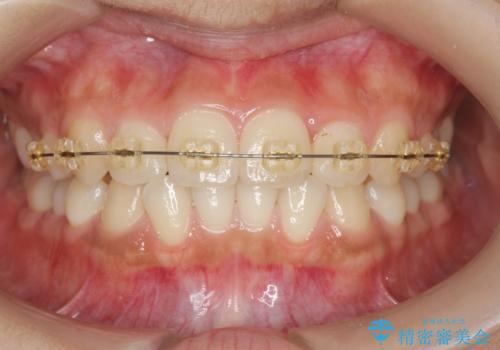

- 前歯のガタつき、上下たがい違いになっている歯並び(クロスバイト)の改善を求めて来院されました。

インビザラインによる矯正治療を行いますが、クロスバイトの改善をワイヤー部分矯正で事前に行うことにより治療期間の短縮する治療計画を立案します。